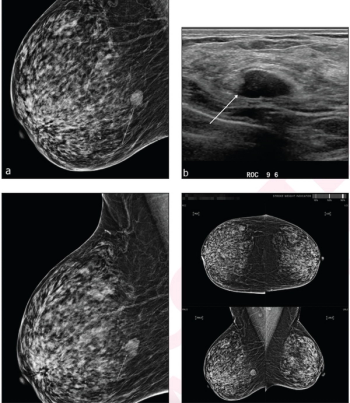

In a new study comparing standard breast MRI, abbreviated breast MRI and contrast-enhanced mammography in supplemental breast cancer screening, researchers found that MRI offered a greater than 14 percent higher cancer detection rate and a nearly 39 percent higher sensitivity rate than CEM.

In a large retrospective study involving over 523,000 digital breast tomosynthesis (DBT) exams and over one million digital mammography (DM) exams, researchers found that DBT was associated with significantly lower recall rates but showed no advantage over DM in the diagnosis of interval or advanced breast cancer.